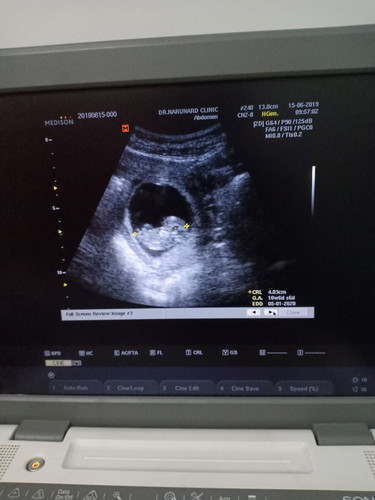

อัลตร้าซาวด์

10w+6 เจอน้องแล้วจ้า เพิ่งไปซาวด์มาเมื่อเช้านี้ ก่อนหน้านี้เคยไปซาวด์ตอน 6w+1 เจอแต่ถึงตั้งครรภ์ หมอบอกว่าเสี่ยงจะท้องลมเพราะแม่อายุเยอะแล้ว ใจแป้วอยู่เหมือนกัน พอมาวันนี้เจอน้องสบายใจขึ้นแล้วค่ะ?